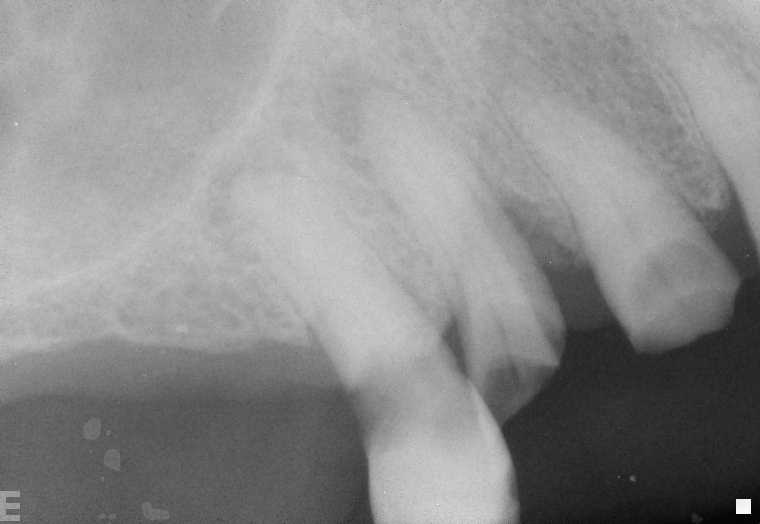

DIGITAL XRAY OF ABCESS

The shadows at the end of the roots are dental abcesses.  Although not always painful, if not treated can really hurt.  These teeth can be saved and used as supports for an over denture. It may be possible to remove teeth, allow the area to heal and place implants which may a longer life expectancy.